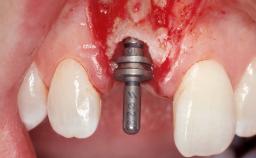

A 30-year-old female patient had lost tooth 21 and was referred to our clinic for consultation and treatment. Due to advanced apical infection, tooth 21 had been extracted two months earlier at another clinic and an acrylic-resin tooth had been bonded to the adjacent teeth. The patient desired implant treatment to avoid any damage to the adjacent natural teeth. While the patient had no history of any systemic disorder, she was a heavy smoker and exhibited medium to advanced periodontitis in the entire jaw. After the initial treatment to achieve a pocket probing depth of less than 4 mm and no bleeding on probing, a decrease in the height of the papillae mesial and distal to the extraction site and overall gingival recession were observed.

Type of Implants | One-Piece|Reduced-Diameter |

Attachment | One-Piece|Reduced-Diameter |

Bone Augmentation | Horizontal|Staged |

Augmentation Materials | Autogenous chips|Membrane |